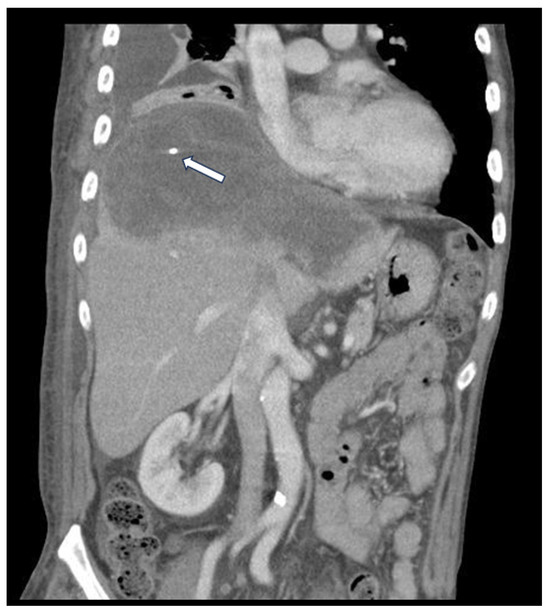

2. Case History